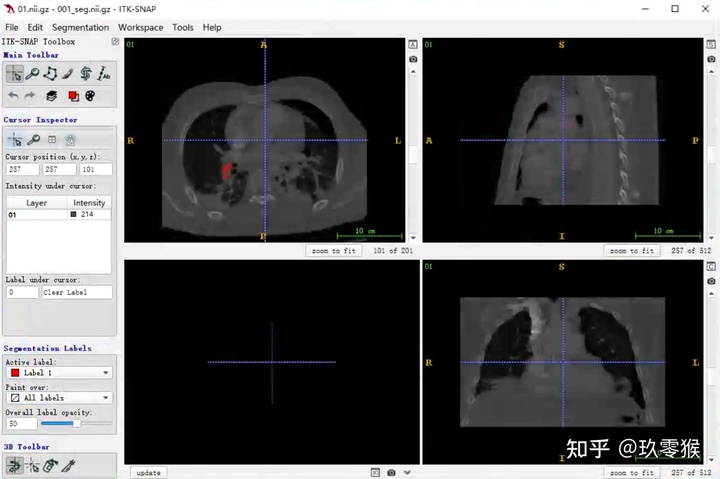

2、载入相应的分割图数据( nii.gz文件)

Segmentation - > Open Segmentation -> Browse... -> Next

3、3D可视化

左键可以选装3D图像

右键加滚轮可以缩放3D图像

2、载入相应的分割图数据( nii.gz文件)

Segmentation - > Open Segmentation -> Browse... -> Next

3、3D可视化

左键可以选装3D图像

右键加滚轮可以缩放3D图像